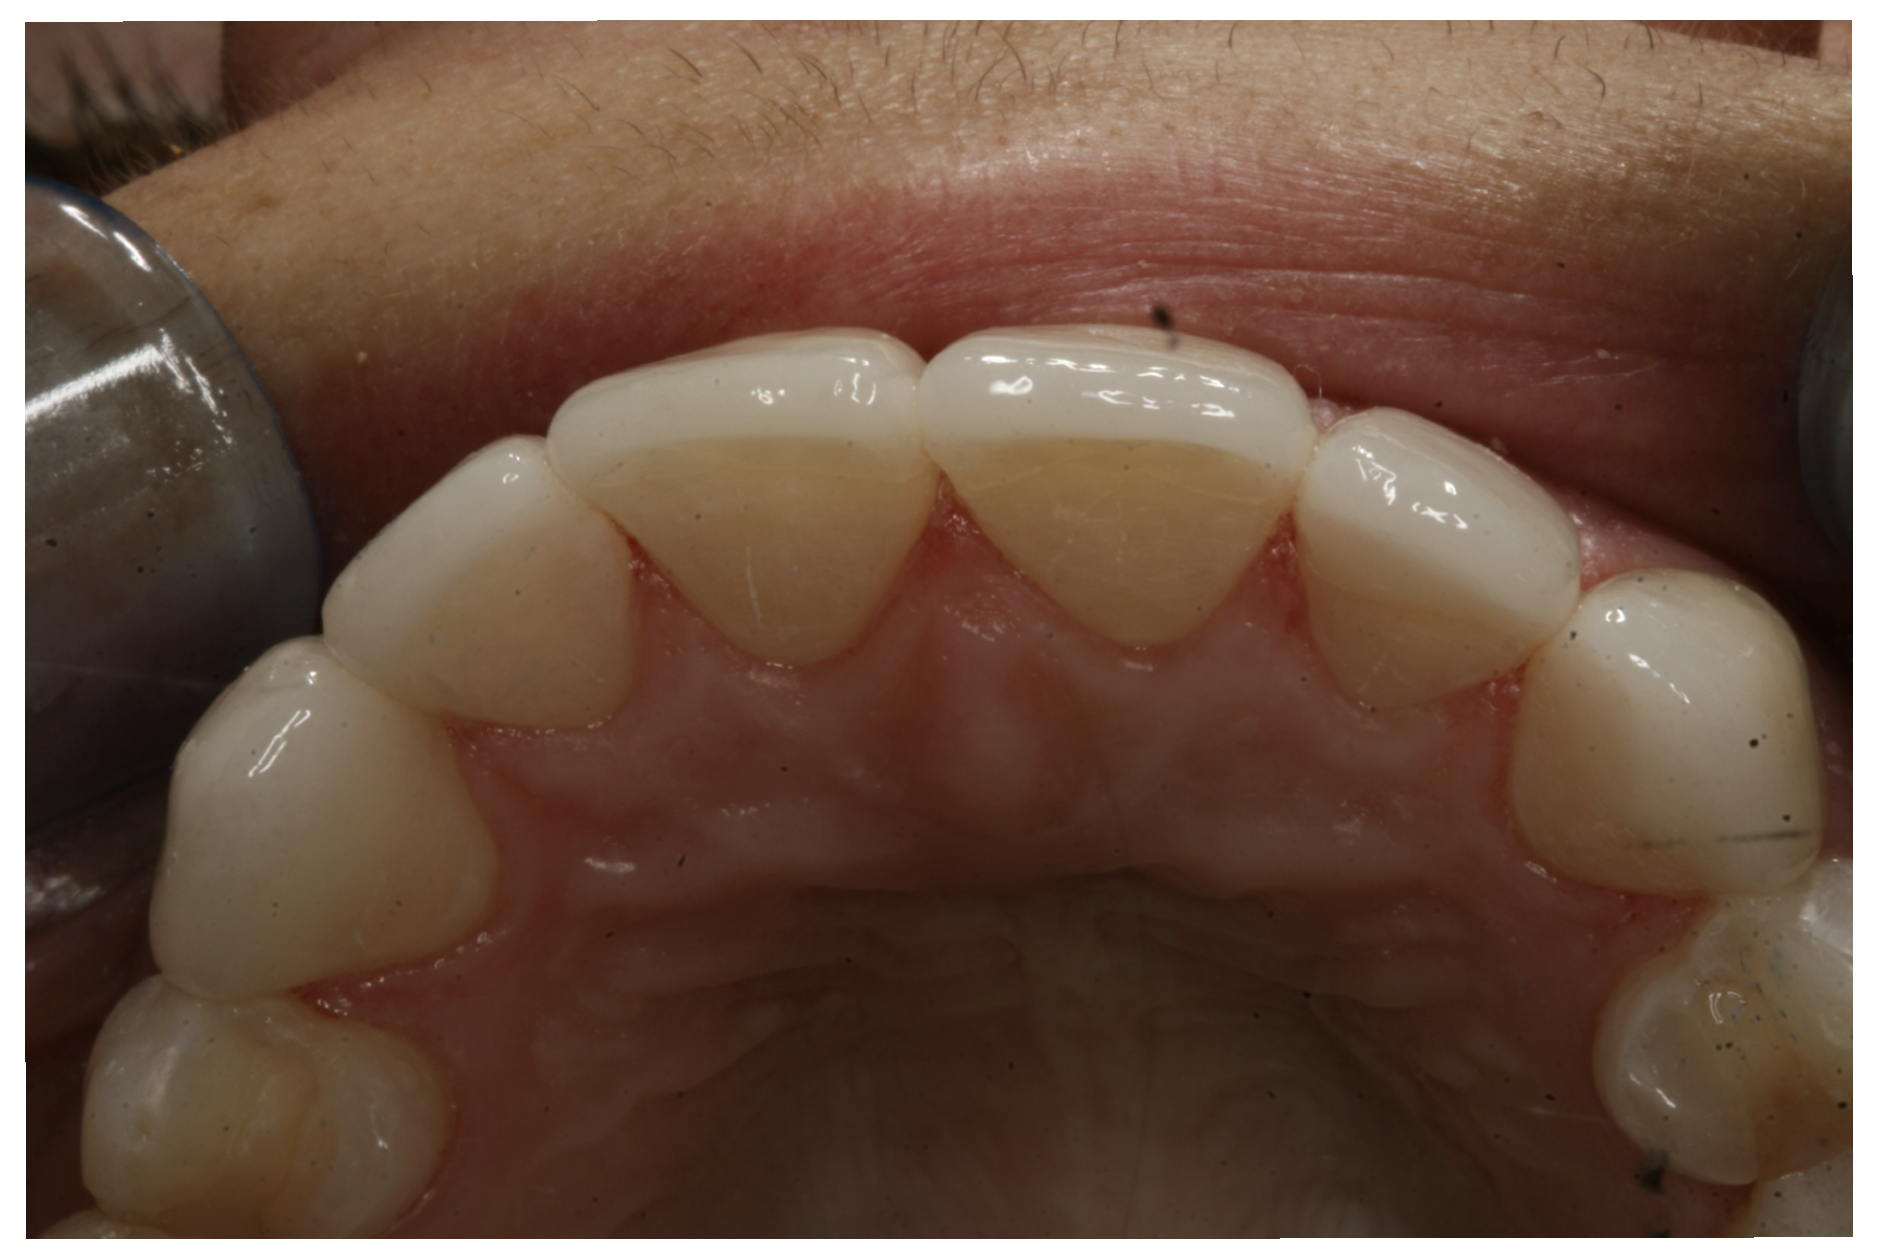

For the case in Figure 9 through Figure 11, the patent presented for an initial consultation with bonding completed on teeth Nos. 7 through 10 a few years prior with a chief complaint of not liking the way the resin bonding looked and how it was wearing. Up to this point, the bonding had repeatedly chipped and been repaired three times already. The patient's canines also exhibited signs of incised wear and flattening, which she did not like. Based on the patient's goals for her smile and her financial budget, she elected to have porcelain veneers completed on teeth Nos. 6 through 11. The total esthetics of the case design were somewhat limited given that the patient's esthetic zone included her posterior teeth and mandibular anterior teeth. Therefore, the color and characteristics of the veneers had to match her existing dentition closely.

In another case, the patient presented with very thick, bulky, over-contoured veneers done on teeth Nos. 7 through 10 when she was a teenager. There also was some recession and staining at the margins (Figure 12). The clinician decided to restore teeth Nos. 6 through 11. A preparation design was required with provisionals removed. As tooth structure could not be regrown, the practitioner made the best of the situation. There was good gum health, which is important for isolation and marginal seal. The clinician cemented with a universal, doing six units at one time. Minimal cleanup was required. At a 1-month follow-up visit, although tissue still was settling in, the contours were natural. After a year (Figure 13), the gum filled in nicely and was in excellent health, and there was good color stability and seamless marginal integrity.